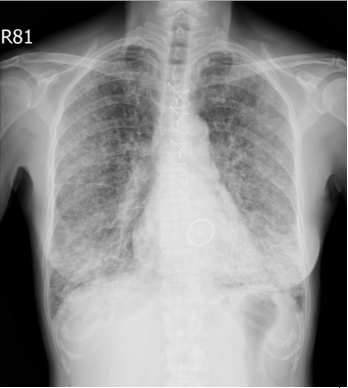

10. 35歲年輕女性,因健檢照了一張胸部X光,如下圖所示,此外,患者在小腿上有皮膚病兆,經診斷為結節性紅斑(erythema nodosum),請問下列哪些敘述正確 1. 需要轉介眼科醫師進行眼睛的評估 2. 該疾病的分期需要進一步使用電腦斷層進行分期 3. 所有患者均需接受治療 4. 該疾病容易造成多重器官侵犯 5. 所有患者的診斷均需要病理切片的檢查 (A) 1+3+4+5 (B) 1+2+4 (C) 1+4 (D) 2+3 (E) 2+4+5